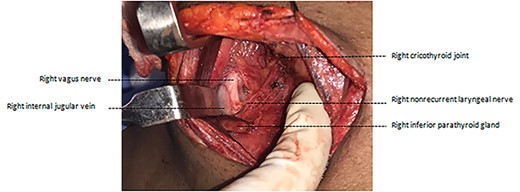

Total thyroidectomy was carried out using intraoperative nerve monitoring with the Medtronic NIM-NEURO 3.0® nerve integrity monitoring system. During dissection, left side RLN was identified in the usual way in the tracheoesophageal groove. On the right side, an NRLN was identified (Fig. 3). It was arising from the right vagus nerve at the level of first tracheal ring, and then ascended upwards and anteriorly to the laryngeal entry point at the right cricothyroid joint. The branches of the inferior thyroid artery were seen to course superficial to the nerve (NRLN type 2b) [1] (Fig. 4). The course of the nerve in the neck was almost perpendicular to the tracheoesophageal groove rather than parallel to it. This nerve was identified at the entry point and was dissected retrograde and preserved in continuity.

Intraoperative photograph after ligation of branches of the inferior thyroid artery.